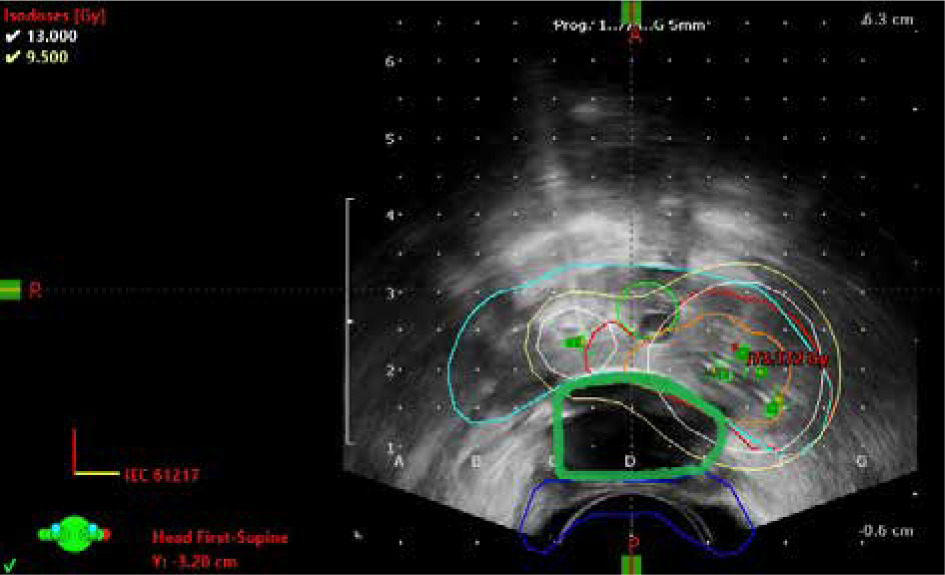

Fig. 2

Axial planning ultrasound plane from fraction 1 with prescribed dose being 12.6 Gy. Image shows gross tumor volume (orange), planning tumor volume (red), prostate (blue), and urethra (green), with isodose doses distributions of 130% (white) and 100% (yellow). Rectal balloon spacer implant (RBI) is marked green between prostate (light blue) and rectum (dark blue)

First, a RBI was implanted to maximally decrease the radiation dose to the rectum. The RBI (ProSpace™, BioProtect Inc., Kfar-Saba, Israel) was implanted transperineally between the Denonvilliers’ fascia and the rectum under trans-rectal ultrasonography guidance. The injection technique has been described previously [19]. The RBI was placed just before the start of the first HDR procedure in November, 2018. Gross tumor volume (GTV) was delineated on ultrasound imaging using PSMA-PET CT scan. The margin for clinical target volume (CTV) was 3 mm according to a local protocol. The urethra and the RBI were excluded from CTV (Figure 2). Specifications of the two HDR sessions are presented in Table 1 [20]. Volumes of the prostate and the treated volumes of GTV and CTV were 26.6, 2.8, and 5.9 cc, respectively.